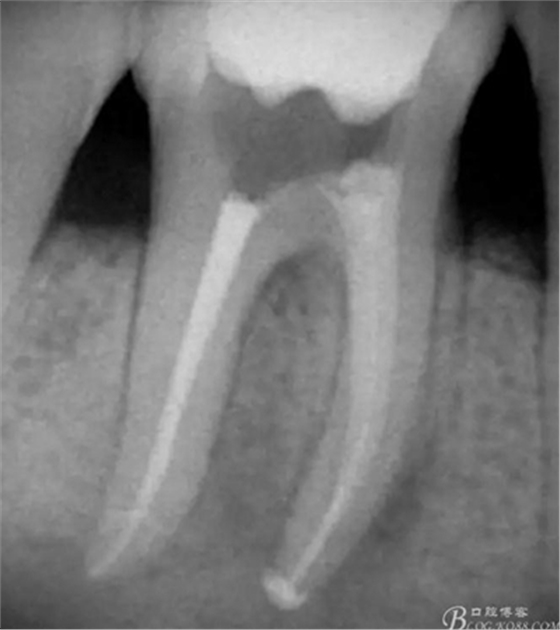

高嵌體粘固后X片